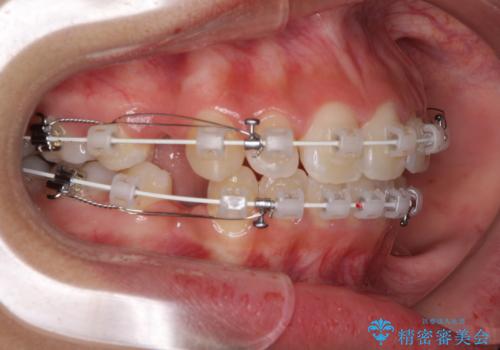

くちばしのように突出した前歯 口元を下げる抜歯矯正

- 審美装置

- 上下の出っ歯を気にして来院された患者様です。

口元を積極的に引っ込めるために、上下左右の第一小臼歯を4本抜歯することとしました。

前歯部の突出と開咬は、舌突出癖によるものでしたので、舌のトレーニングをしっかりと行っていただき、1年半程度と短期間で治療を終えることができました。